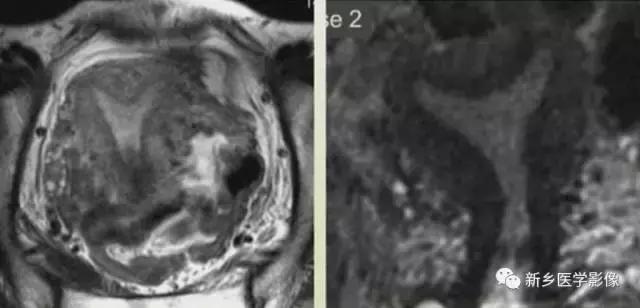

完全型纵隔子宫:短T2信号纵隔贯穿宫腔,宫颈管及阴道上段。

MR诊断为完全型纵隔子宫伴阴道纵隔。

完全型纵隔子宫:宫底平坦,纵隔贯穿宫腔和宫颈

不完全型纵隔子宫:宫底平坦,纵隔未达宫颈内口水平